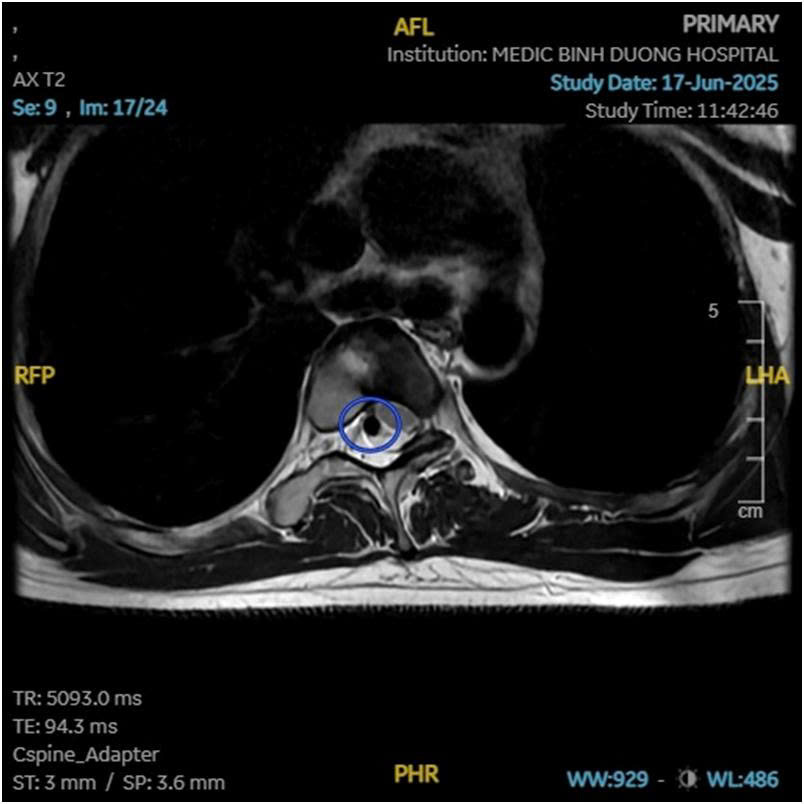

Hình 2: Bất thường mạch máu trong ống sống đi kèm.

Nếu con bạn, đặc biệt là ở lứa tuổi dậy thì, có dấu hiệu đau lưng không rõ nguyên nhân, vai lệch, hoặc một bên hông cao hơn bên kia, đừng bỏ qua. Hãy đưa trẻ đi khám bác sĩ chuyên khoa cột sống. Các phương pháp chẩn đoán hình ảnh như chụp X-quang, CT scan (chụp cắt lớp) hoặc MRI (chụp cộng hưởng từ) sẽ giúp bác sĩ xác định chính xác tình trạng đốt sống bán phần và mức độ cong vẹo.

Điều quan trọng cần biết là, dị tật đốt sống bán phần thường không xuất hiện đơn độc. Nó có thể là tín hiệu cảnh báo cho nhiều bất thường tiềm ẩn khác trong cơ thể, đặc biệt là ở tim, thận hoặc các hệ cơ quan quan trọng khác. Chính vì vậy, câu chuyện của em không chỉ là hành trình tìm kiếm sự chữa lành cho cột sống, mà còn là lời nhắc nhở khẩn thiết về tầm quan trọng tối đa của việc đi khám bệnh sớm và toàn diện khi phát hiện bất kỳ dấu hiệu bất thường nào. Đừng bỏ qua những triệu chứng nhỏ, vì chúng có thể là manh mối dẫn đến một chẩn đoán quan trọng, mở ra cánh cửa cho việc can thiệp kịp thời và bảo vệ sức khỏe tổng thể của trẻ.